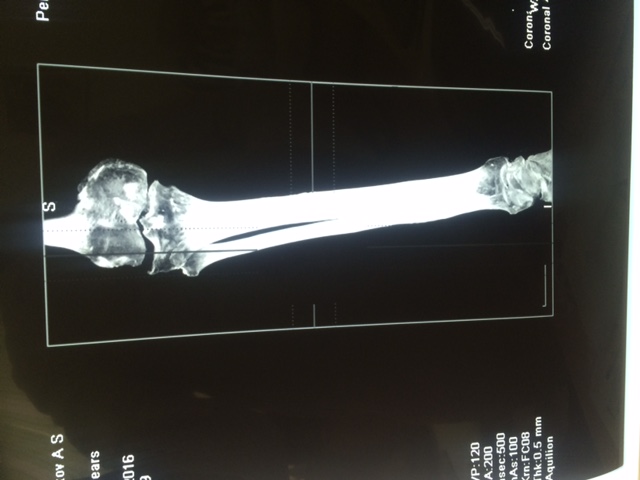

Операция по поводу Hallus Rigidus c использованием современных имплантов системы IO-FIX

Сложная плоско-вальгусная патология стопы Артродез таранно-ладьевидного сустава , 1 плюснеклиновидного сустава, артродез пяточно-кубовидного сустава

Использованы комбинированные методы реконструктивной операции (SCARF+AKIN+ WILSON+ подкожные методы остеотомии малых лучей на левой и правой стопе)

Сложная стопа с выраженным поперечным плоскостопием выполнен ряд оперативных методик реконструкции переднего отдела стопы (SD+AKIN+PROXIMO+WILSON+ WEIL) Использованы импланты SFM, SIF

Сложная прогрессирующая деформация стопы на фоне ревматоидного полиартрита. Выполнены множественные комбинированные методы хирургической коррекции (SD+ AKIN+ артродез LAPIDU + ряд малоинвазивных подкожных остеотомий малых лучей на уровне проксимальных фаланг 2,3,4 пальца ) Использованы специальные импланты винты SFM, титановые скобы и подкожная фреза для аппарата АОК УНИ -01